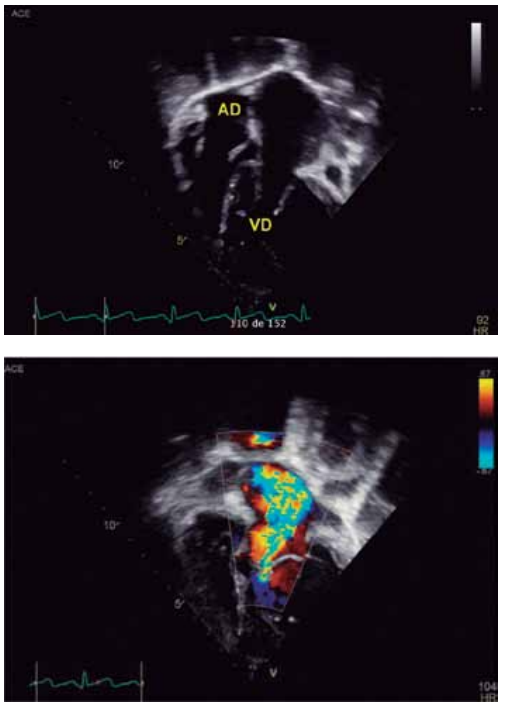

Para responder à questão, considere as imagens

ecocardiográficas a seguir, de uma criança de 12 anos, com

cardiopatia congênita.

Dados: AD = átrio direito; VD = ventrículo direito.

(Arquivo pessoal; imagens usadas com autorização)